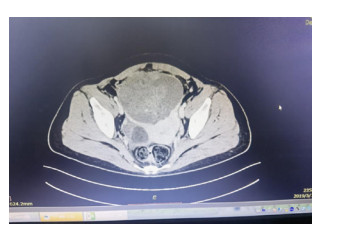

1 资料与方法患者,女,33岁,因“急起胡言乱语、行为异常10 d”于2019年4月21日收治于杭州市第七人民医院。4月11日患者因工作压力大在单位突然情绪崩溃,胡言乱语,行为异常,后回家休息。在家中,患者间歇性通过哭泣、叫喊发泄情绪,彻夜不眠,大声咒骂,情绪异常激动,送至杭州市第七人民医院住院治疗。入院后查血常规、生化全套、甲状腺功能、头颅CT等无异常,诊断考虑:焦虑状态、精神障碍、分离转换障碍,给予奥氮平、丙戊酸钠、百忧解等药治疗,效果不佳。5月3日患者突然发热,体温最高达39.1℃,急查血常规:白细胞11.44×109/L,中性粒细胞8.32×109/L,C反应蛋白229.2 mg/L。生化:谷丙转氨酶143.8 U/L,谷草转氨酶78.9 U/L,肺CT示左肺上叶舌段及右肺中叶内侧段慢性炎症或纤维灶考虑。予头孢呋辛抗感染治疗,效果不佳。追问病史,患者诉7年前体检发现畸胎瘤,直径约2.7 cm,无不适,未治疗,后育二女,均无异常。急查腹部CT示:下腹部盆腔内巨大占位,肿瘤首先考虑,畸胎瘤可能性大:右侧附件区低密度灶; 盆腔少量积液。因患者感染控制不理想,精神症状稍好转,遂出院。至本地某三甲医院就诊,复查血常规:白细胞15.9×109/L,中性粒细胞12.62×109/L,C反应蛋白239.4 mg/L。生化:谷丙转氨酶117 U/L,谷草转氨酶69 U/L。凝血酶原时间14.6 s,D-二聚体5 520 μg/L。予头孢类抗生素静滴,体温控制不佳,并出现腹部绞痛。为求进一步诊治于2019年5月13日以“发热待查”入树兰医院感染科。患者入院后仍反复高热,炎症指标高,全腹平扫+增强CT示:双附件区及下腹腔多发占位,考虑多发畸胎瘤,较大病灶破裂可能,腹盆腔积液(图 1),头颅MRI无异常。5月16日组织感染科、胃肠外科、妇科、精神科等多学科会诊(MDT)。感染科认为患者目前双侧畸胎瘤伴破裂,腹腔继发感染明确,曾有精神神经症状,故尚需排除脑炎; 胃肠外科认为患者目前盆腔肿块卵巢肿瘤诊断明确,建议:⑴先确定脑炎与肿瘤的关系; ⑵手术治疗; ⑶若同结肠有关,术中同时处理。精神科认为患者短期出现言行异常、情绪不稳定、遗忘、烦躁等多种精神症状,在杭州市第七人民医院住院治疗期间,又出现了高热、意识障碍、痫性发作等情况,起病急,精神症状变化快,考虑患者精神症状可能与畸胎瘤有关,建议完善腰穿检查,排除自身免疫性脑炎(NMDA抗体)所致精神障碍。妇科认为患者已婚育,发现畸胎瘤7年,突发腹痛、精神症状、发热等,CT提示盆腔巨大包块,不排除畸胎瘤破裂感染粘连可能,建议:⑴患者目前不排除畸胎瘤与精神症状、自身免疫性脑炎相关,故完善NMDA抗体检测,如能明确则行双侧切除,术后相关激素替代治疗,如非自身免疫性脑炎,则术中尽可能保留卵巢功能。⑵控制感染,完善检查后转妇科手术治疗。5月19日查腰穿结果提示:脑脊液抗谷氨酸受体(NMDA型)抗体IgG+ 1∶10,诊断自身免疫性脑病明确,考虑患者精神症状与畸胎瘤关系密切,且畸胎瘤较前进展快,恶变可能,局部小破裂,腹腔感染明确。在感染科予抗炎、护肝、抗精神病等治疗后患者病情有所控制,5月21日转妇科进一步诊治。完善术前准备,于5月28日行“腹腔镜下双侧卵巢囊肿剥除术+左侧输卵管切除术+盆腔粘连分离术+肠粘连松解术”,术中见子宫前位,正常大,表面光滑,形态正常; 左侧卵巢冠囊肿增大约10 cm×11 cm×9 cm,与左输卵管一起顺时针扭转1.5圈,左侧输卵管增粗水肿。大网膜、乙状结肠和左侧卵巢冠囊肿致密粘连; 右侧卵巢分别见大小约3 cm×2 cm及2 cm×2 cm囊肿,右侧输卵管外观无殊。术中及术后病理均提示:⑴(左卵巢)成熟性畸胎瘤伴神经组织及坏死; ⑵(右卵巢)成熟性畸胎瘤(图 2)伴甲状腺肿。术后4 d,复查血常规+超敏C反应蛋白,白细胞计数3.7×109/L,中性粒细胞百分比58.8%,超敏C反应蛋白8.2 mg/L,患者恢复良好,停用抗生素。精神科会诊患者精神症状完全消失,接触交谈如常人。出院后随访:患者出院后未再服用精神类药物,继续免疫治疗[3]。随访1年,患者无明显精神症状,工作生活如常人。

| 图 1 患者2019-05-14全腹CT平扫+增强结果(示双附件区及下腹腔多发占位) |